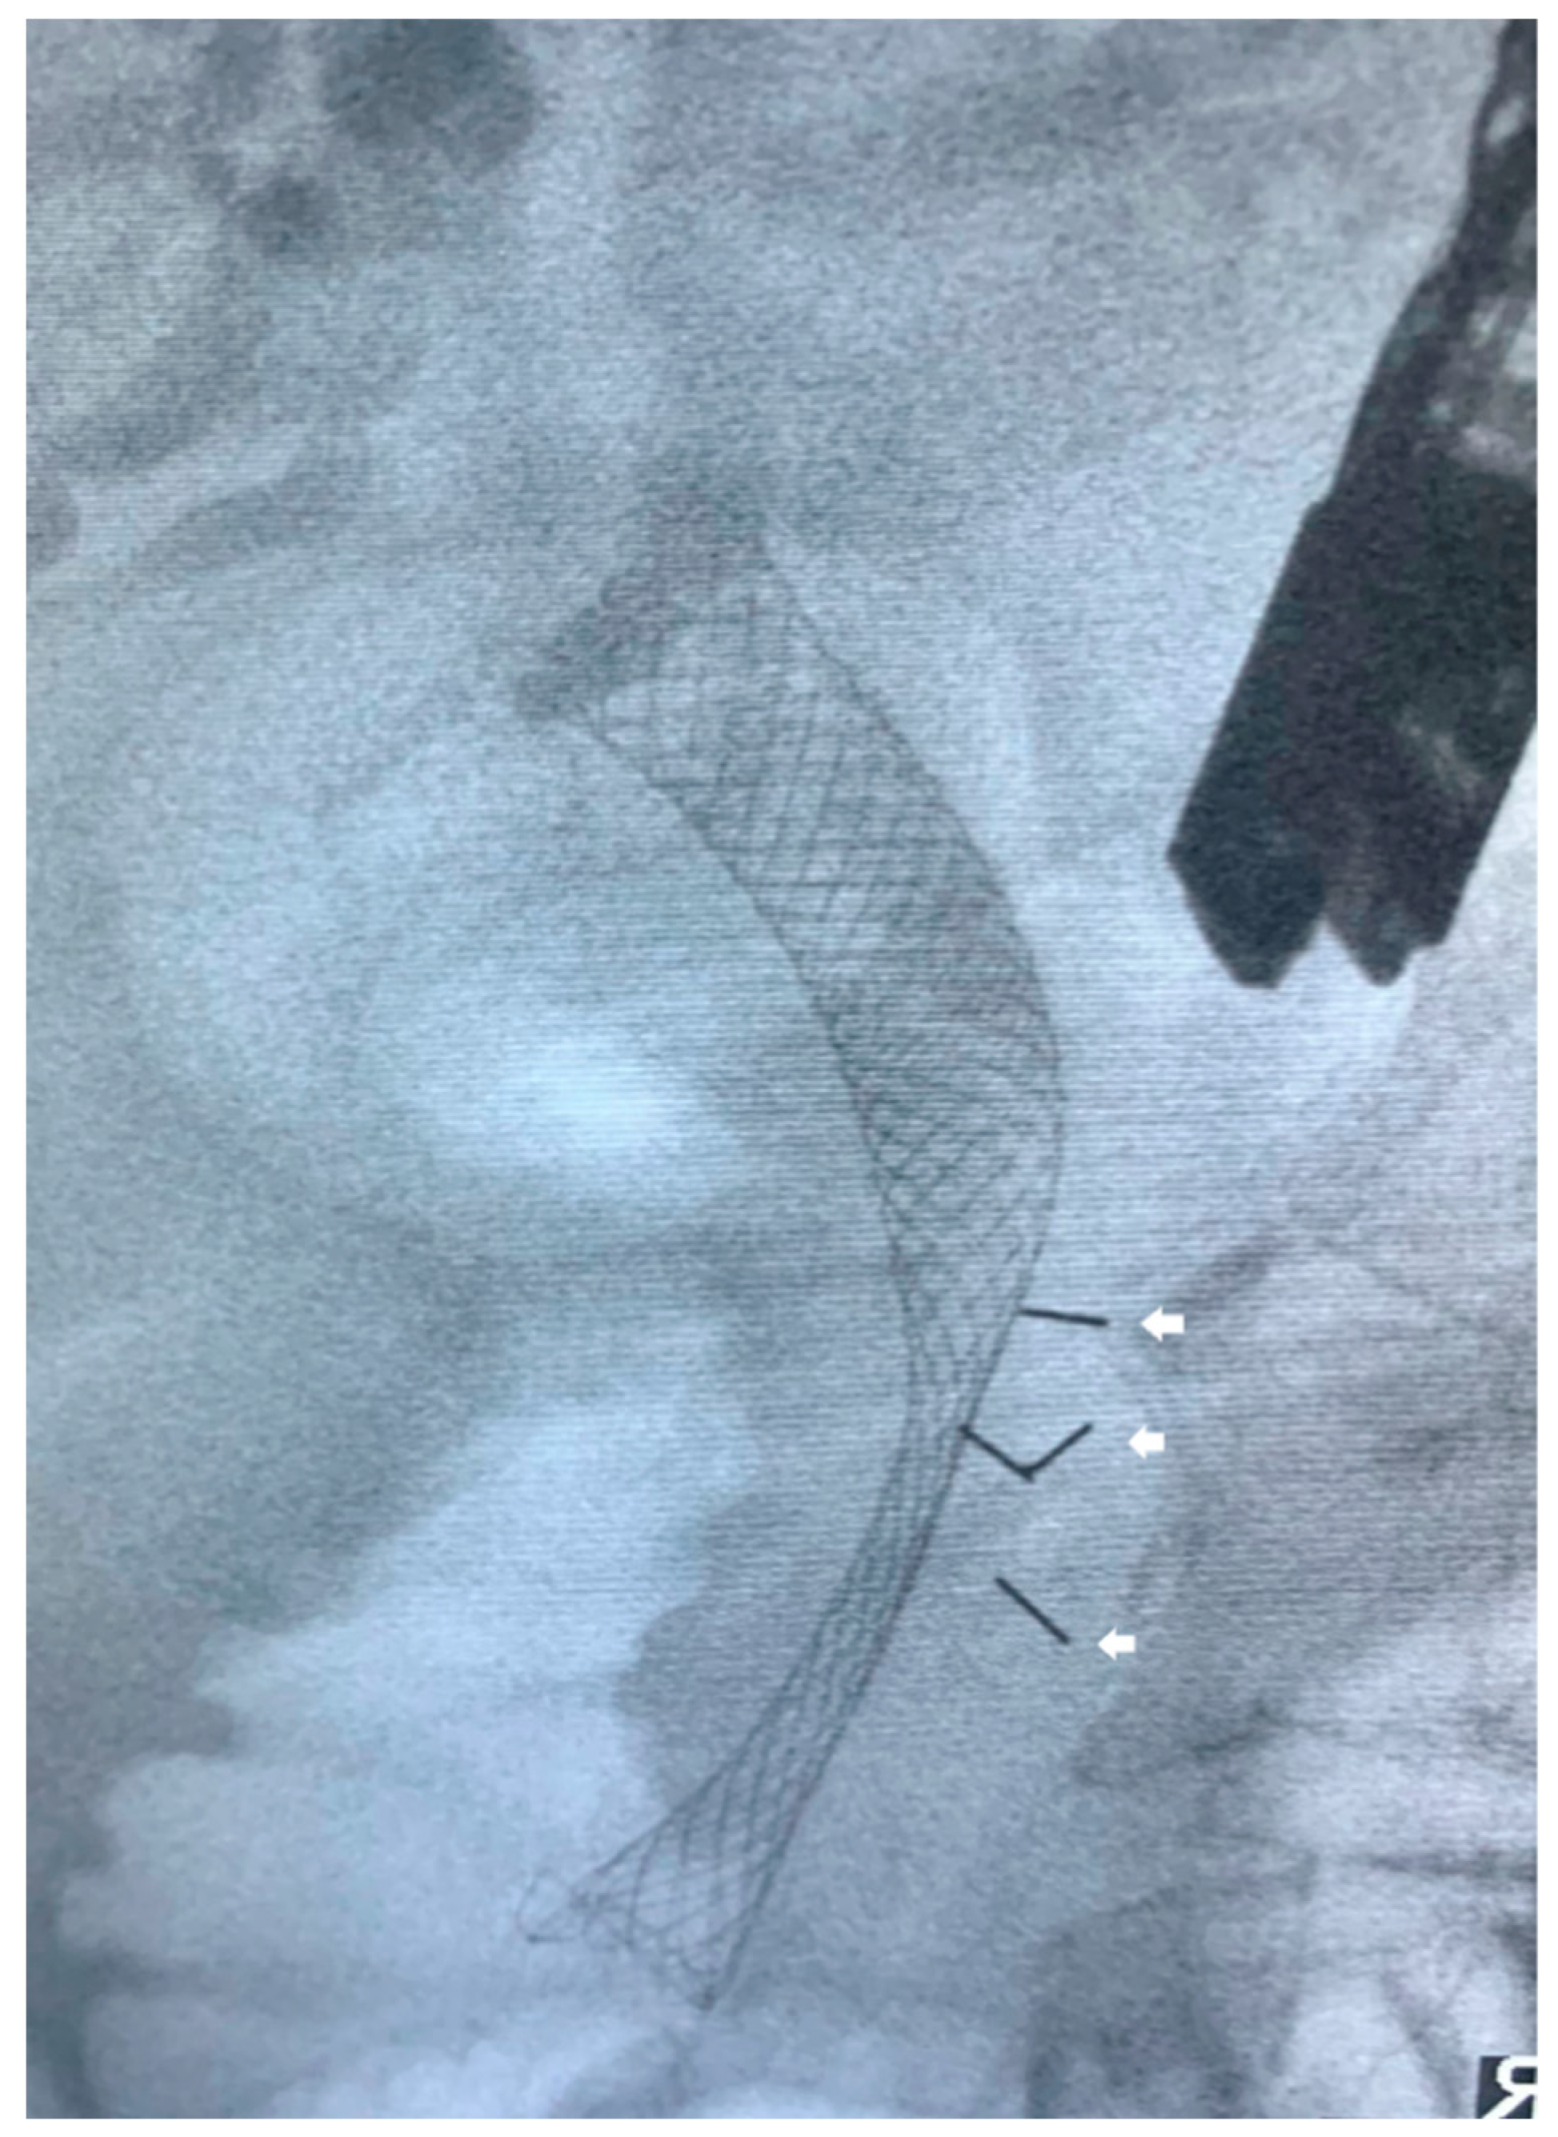

- Dávila Fajardo, R.; Lekkerkerker, S.J.; van der Horst, A.; Lens, E.; Bergman, J.J.; Fockens, P.; Bel, A.; van Hooft, J.E. EUS-guided fiducial markers placement with a 22-gauge needle for image-guided radiation therapy in pancreatic cancer. Gastrointest Endosc. 2014, 79, 851–855. [Google Scholar] [CrossRef] [PubMed]

- Dhadham, G.C.; Hoffe, S.; Harris, C.L.; Klapman, J.B. Endoscopic ultrasound-guided fiducial marker placement for im-age-guided radiation therapy without fluoroscopy: Safety and technical feasibility. Endosc. Int. Open 2016, 4, E378–E382. [Google Scholar] [PubMed]

- Tabernero, S.; Prados, S.; Rubio, M.D.C.; de la Morena, F.; López, M.; Sánchez, E. Endoscopic ultrasound-guided fiducial placement in pancreatic tumors: Safety and technical feasibility. Rev. Esp. Enferm. Dig. 2019, 111, 425–430. [Google Scholar] [CrossRef]

- Khashab, M.A.; Kim, K.J.; Tryggestad, E.J.; Wild, A.T.; Roland, T.; Singh, V.K.; Lennon, A.M.; Shin, E.J.; Ziegler, M.A.; Sharaiha, R.Z.; et al. Comparative analysis of traditional and coiled fiducials implanted during EUS for pancreatic cancer patients receiving stere-otactic body radiation therapy. Gastrointest. Endosc. 2012, 76, 962–971. [Google Scholar] [CrossRef]